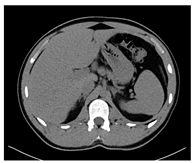

| CT-scan | ![]() | ![]() | ![]() |

| Elasticity (Kilopascal—kPa) | Ultrasounds Attenuation (dB/cm/MHz) | Shear Wave Speed (m/s) | CT-Scan Density (Hounsfield Unit—HU) | MRI–T1 Signal Intensity (SI-a.u.) | MRI–T2 Signal Intensity (SI-a.u.) | Fracture Force (Kilonewton—kN) | |

|---|---|---|---|---|---|---|---|

| G8 | 7.67 | 0.04 | 1.60 | 52.29 | 1012.7 | 1355.4 | 0.23 |

| G12 | 11 | 0.10 | 1.9 | 71 | 1329.1 | 808.5 | 0.30 |

| G14 | 13 | 0.09 | 2.08 | 82.07 | 1458.1 | 1103.3 | 0.55 |

| G16 | 5.84 | 0.12 | 1.39 | 92.32 | 1607.6 | 890.1 | 0.38 |

| G14i5 | 30.9 | 0.15 | 3.21 | 83.25 | 1489.4 | 1642.7 | 0.50 |

| G14i10 | 33 | 0.20 | 3.32 | 80.73 | 1547.6 | 1289.6 | 0.52 |

| G14i15 | 39.2 | 0.28 | 3.62 | 71.5 | 1223.6 | 1863.7 | 0.67 |

| G14alc10 | 14.9 | 0.08 | 2.23 | 70.75 | 917.5 | 2162.3 | 0.38 |

| G14alc20 | 23 | 0.11 | 2.77 | 60.43 | 1054.4 | 1904.5 | 0.38 |

| G14s32:17.5 | 38.3 | 0.93 | 3.57 | 74.87 | 1025.6 | 1574.6 | 1.13 |

| G14s32:15 | 32.7 | 0.71 | 3.30 | 65.69 | 993.3 | 1414.6 | 2.01 |

| G14s32:12.5 | 35.45 | 0.71 | 3.44 | 64.75 | 1333.6 | 1336.2 | 2.16 |

| G14s32:10 | 27.1 | 0.75 | 3 | 50.85 | 1144.6 | 1314.8 | 2.28 |

| G14s32:7.5 | 35.15 | 0.67 | 3.42 | 49.9 | 1398.8 | 1397.4 | 1.81 |

| Pig liver (ex vivo) | 32.1 | 0.94 | 3.27 | 76.06 | 1131.5 | 176.1 | 1.26 |

| Human normal liver | 4.5 4.8 [27] 4.93 [28] | 0.5 0.552 ± 0.03 [29] 0.5 (normal)–1.1 (severe steatosis) [30] | 1.23 1.3 [27] | 51.02 42 [31]–58.32 [32] | 402.1 | 215.4 | N.A. |

| Human fatty liver (with no fibrosis) | 4.47 No significant difference compared to normal liver [33] | 0.56 0.69 [34] | 1.22 3.42 [34] | 36.1 32.44 [32]–64 [32] | 453.83 | 282.7 | N.A. |

| Human cirrhotic liver | 35.8 14 [27] 25.8 [35] 27.5–62.7 [36] 13.29 [28] | 0.5 0.58 [34] | 3.45 2.2 [27] 2.61 [34] | 50.46 50.59 [32] | 363.38 | 188.95 | N.A. |